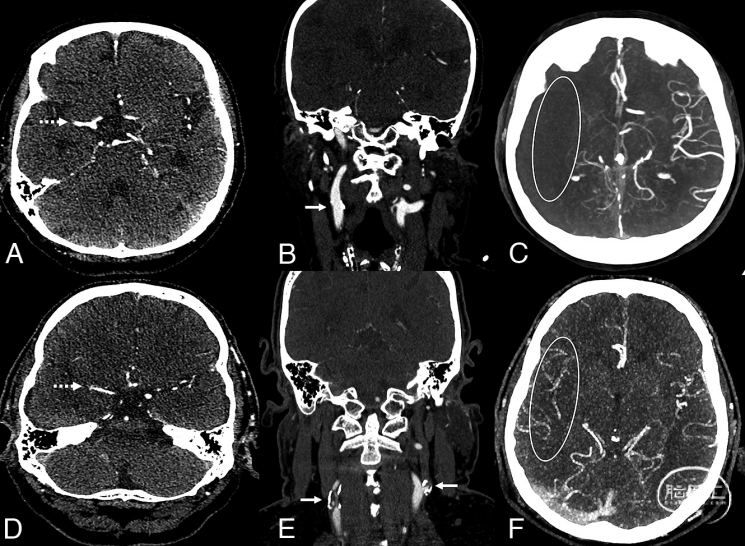

该研究为单中心、回顾性研究,纳入了2015年1月至2021年12月期间因大脑中动脉M1段闭塞接受取栓的患者。研究评估了CAD情况,定义为同侧严重狭窄,即狭窄率≥70%或闭塞。根据Tan评分来评估侧支循环代偿情况。Tan评分范围为0-3:0表示无侧支;1表示大脑中动脉闭塞区域1%-50%可见侧支;2表示大脑中动脉闭塞区域51%-99%可见侧支;3表示大脑中动脉闭塞区域100%可见侧支。将Tan评分为3分定义为侧支循环良好,见图1。通过比较随访影像和基线影像的ASPECTS来量化梗死是否增长,将ASPECTS下降1分及以上定义为梗死增长。

图1. 急性右侧大脑中动脉M1段闭塞侧支循环优劣2例(A、D,虚线箭头)。例1无同侧或对侧颈内动脉颅外段狭窄(B,直箭头),颅内侧支循环差,Tan评分0(C)。例2显示同侧和对侧颈动脉病变(E,直箭头),颅内侧支循环好,Tan评分3(F)。